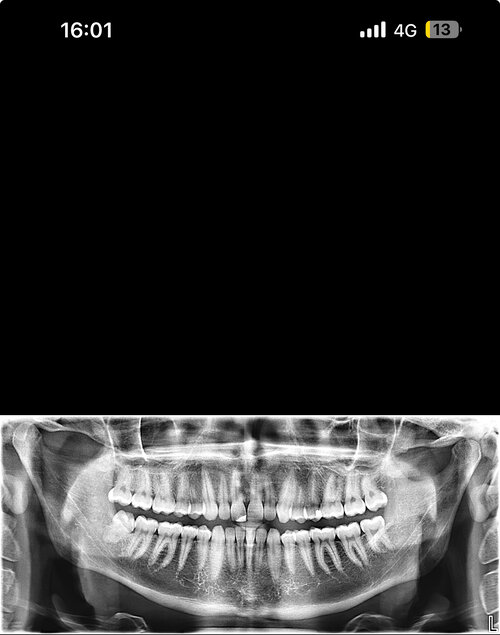

Hello, I’m looking for advice on genioplasty vs DJS. I was planned for a genio 7mm horizontal and squaring of chin on may 11th. I got a second opinion because I thought the oralmaxillofacila surgeon doing my genio might have been downplaying my mandible/maxilla recession. The second opinion oomfs surgeon said that genio would only be a camouflage and for my high expectations, might disappoint me, and I’m starting to think it will. My midface is flat and my mandible from side profile looks short and awful. The problem I have is DJS is a huge commitment for a bigger gain in a year-year and a half time. It’s a lot to take in. But I really don’t want to live my whole life with recessed jaws, I don’t want a soft youthful boyish look especially because I’m getting into my mid 20s, I hate my side profile a lot. Genio will help but I’m extremely worried I’ll be really disappointed, and I can’t really go back if I commit. Looking for advice on if I should go with the genio, see improvement now (which I care a lot about) and get a rhino/septoplasty to fix my deviated septum and be capped by by midface/mandible recession but decently improved, or If I should look awful for another year and a half with braces and my current recession but have the functional and aesthetic benefit of djs at the end. I have extremely bad breathing issues especially during exercise and pretty bad sleep issues, but I don’t know how much to that is down to allergies/deviated septum as opposed to airway issues. I just don’t know what to do, I’ll include my ceph/ct scans and side/front profile photos, would really appreciate guidance on what to do, was thinking of frauding with filler for a year before getting djs, or getting real structural change through rhino braces and genio that would all be down within 7-9 months, thankyou .

• IMG_3957.jpeg

IMG_3957.jpeg

594.2 KB · Views: 0